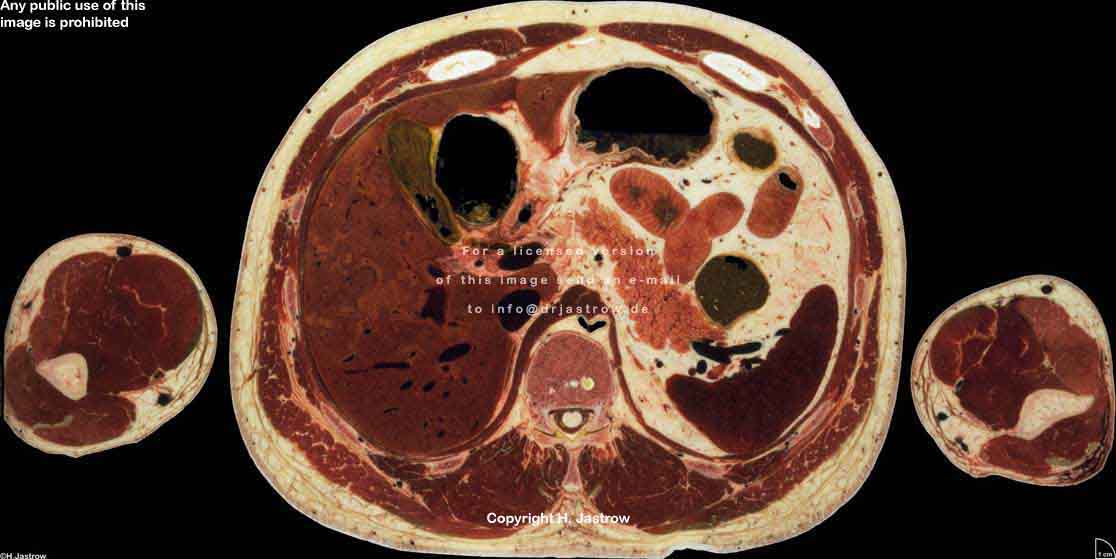

Visible Human male: Sectio transversalis 1554

CT

NMR

Pd                          / T2 \                         T1